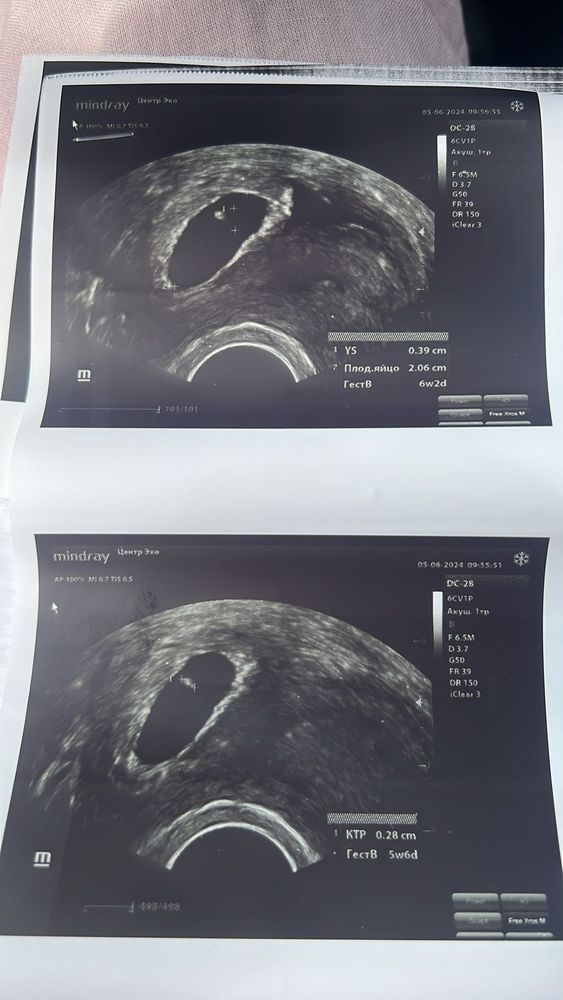

Криоперенос 6 мая(на 20дмц). Первое узи вроде как по сроку ПЯ было (на 21 дпп).

5 июня пошла на повтор, и тут врач начала сомневаться, потом начала считать, чтобы успокоить меня … мол динамика же хорошая, но ктр же маленький…СРОК между узи 9 дней… что лучше смотреть динамику или ктр ? ( врач репродуктолог)

Для такого срока конечно очень маленький ктр… да, безусловно надо смотреть динамику по эмбриону, 3-5 дней и все будет понятно

Irina, так вы ходили на 21дпп:

это 3н5дн (эмбриональных) =>5н5д акушерских;потом

на 30дпп это 4н7д (эмбриональных) => 6н7д (акушерских). У вас всё указано верно.